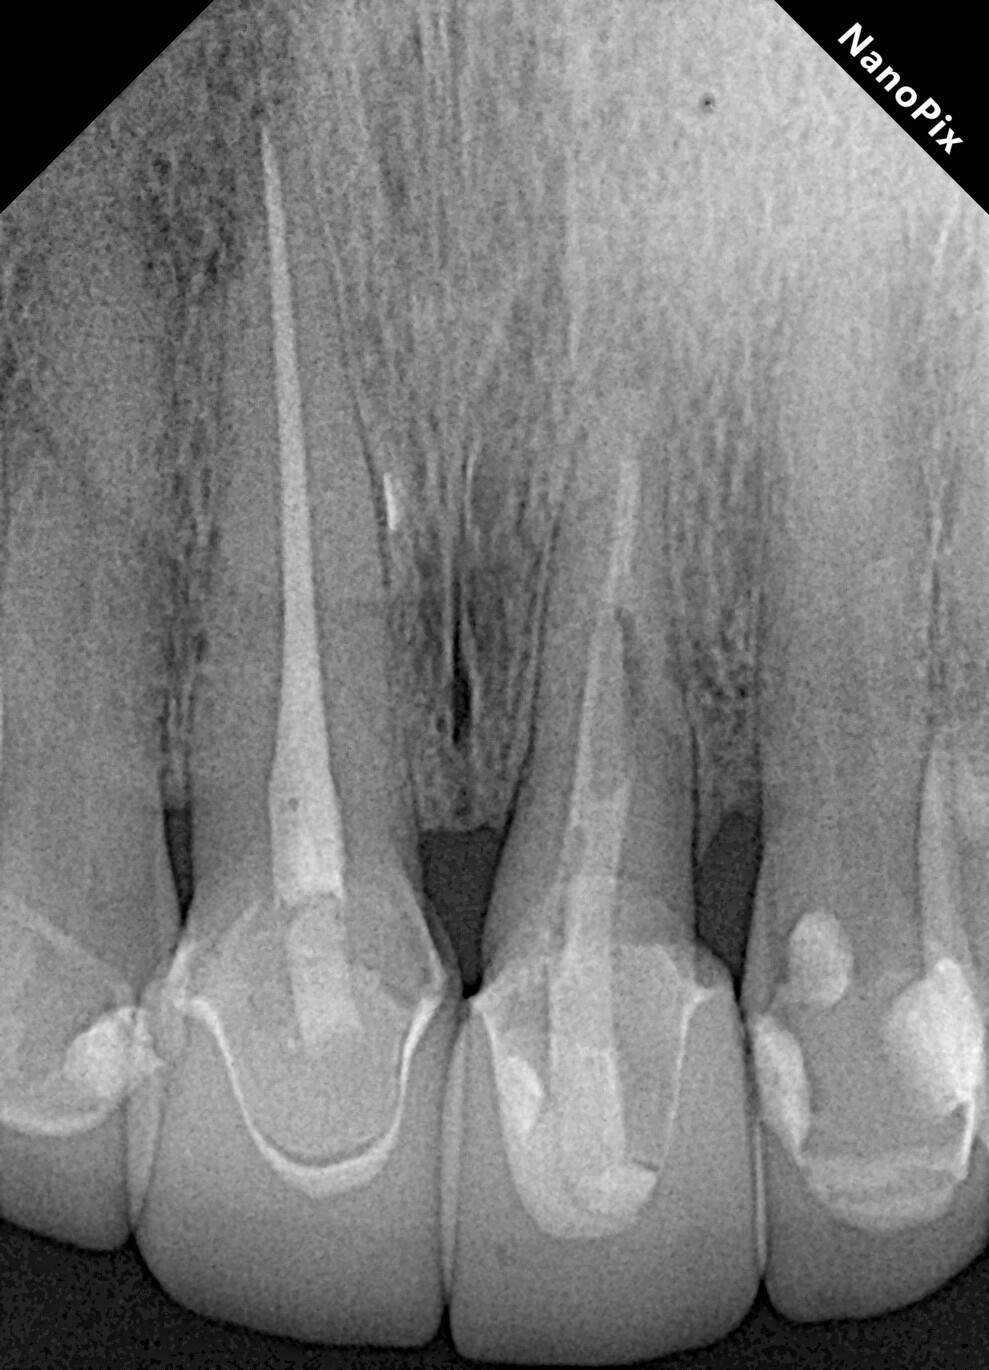

A female patient was evaluated in the dental office after a traumatic event involving her maxillary teeth. She had an oblique fracture from the mesial to distal aspect of the maxillary left central incisor at subgingival level, and the tooth’s metal post and metal–porcelain crown presented with mobility. The tooth had healthy periapical tissue (Fig. 1). Upon radiographic and clinical evaluation, it was noted that there was insufficient dental structure for a predictable restoration.15 Treatment planning included measurement and analysis of the root length, of the width of the root canal walls and of the available supragingival structure. Various treatment options were considered to save the tooth, and after a comprehensive evaluation, surgical extrusion was chosen as the preferred option to achieve adequate healthy supragingival dental structure, thereby offering the patient a favourable long-term treatment solution.6, 8

Fig. 1: Initial clinical radiograph showing tooth #21 with a previous root canal treatment, a metal post, a full-coverage coronal restoration and an oblique fracture from the mesial to distal aspect.